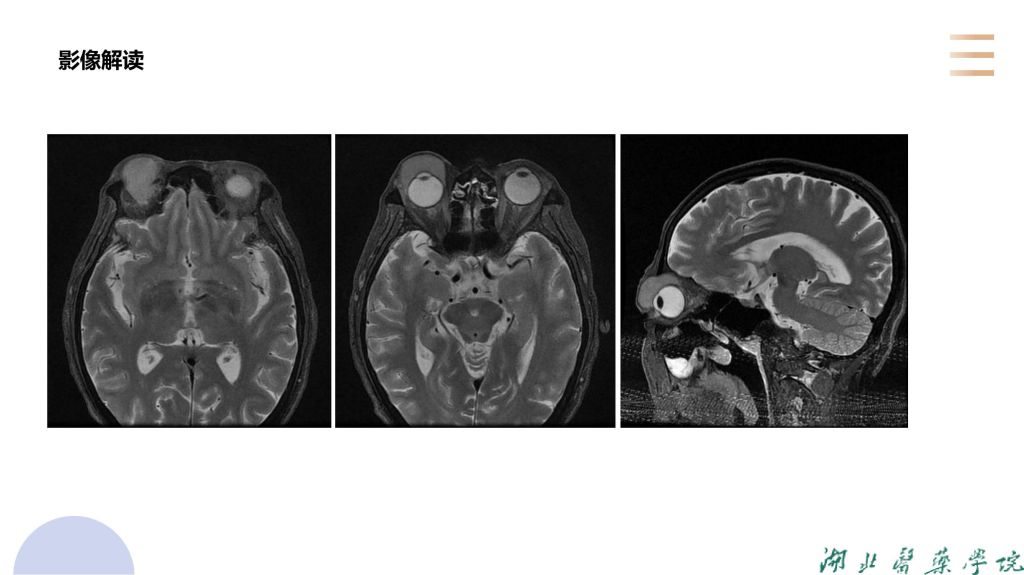

病例分析-眼眶淋巴瘤